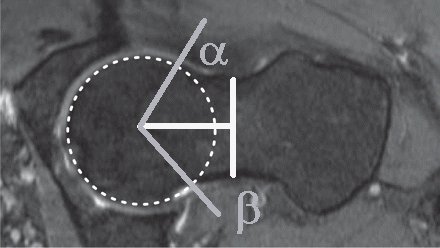

The range of movement before impingement is estimated from sectional images of the hip. A number of parameters have been measured, some completely different measurements have given the same Greek letter! Even reduced to two dimensions there are several parameters to consider:

Notes Clin Orthop Relat Res. 2012 Dec;470(12):3355-60. doi: 10.1007/s11999-012-2477-2. The acetabular wall index for assessing anteroposterior femoral head coverage in symptomatic patients. Siebenrock KA, Kistler L, Schwab JM, Büchler L, Tannast M Loss of rotation due to femoral neck thickening is quantified as the a angle (internal rotation) [ Do normal radiographs exclude asphericity of the femoral head-neck junction? Dudda M, Albers C, Mamisch TC, Werlen S, and Beck M. Clin Orthop Relat R, 2009, 467 (3):651–659. ] and ß angle (external rotation) [ Three-dimensional computed tomography of the hip in the assessment of femoroacetabular impingement. Beaulé PE, Zaragoza E, Motamedi K, Copelan N, and Dorey FJ. J Orthop Res, 2005, 23(6):1286–1292. ]. Available rotation after to acetabular pincer lesions is quantified as over coverage using the lateral centre edge angle, anterior centre edge angle. The combined loss of rotation due to femoral neck thickening and acetabular rim extension/reorientation is